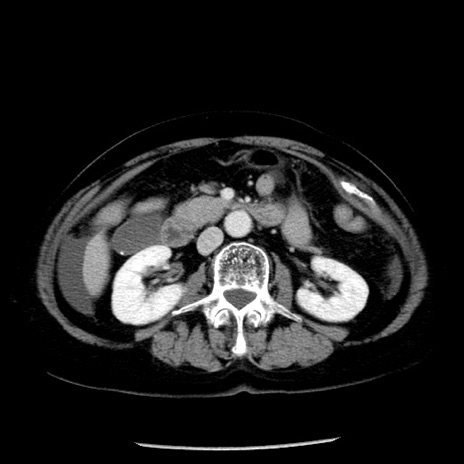

症例13(横断像)

【症例】70歳代女性

【主訴】腹痛、嘔吐

【現病歴】15時間程前(昨晩)より腹痛あり。今朝になっても症状の改善なく、嘔吐あり。腹痛も増悪あり、救急外来受診。

【既往歴】子宮癌全摘術後

【身体所見】意識清明、BP 121/72mmHg、P 74bpm、SpO2 100%(RA)、腹部:平坦・軟、腸雑音ほぼ聴取せず。下腹部・心窩部・臍左上に圧痛あり。反跳痛なし。

【データ】WBC 10600、CRP 0.15